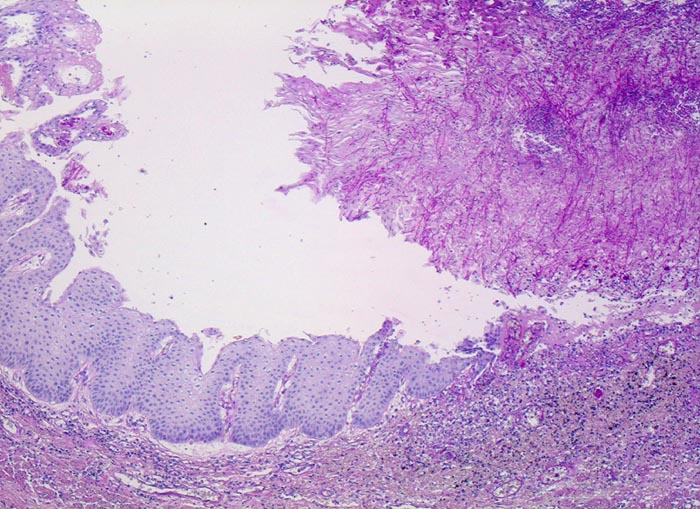

Endoskopisch finden sich abstreifbare weissgelbe krümelige Plaques, welche keine Prädilektionsstelle zeigen. Die Schleimhaut kann erodiert oder ulzeriert sein. In Klumpen von nekrotischen Plattenepithelzellen lassen sich mikroskopisch oft Sporen und Pseudohyphen nachweisen. Die Pseudohyphen wachsen oft senkrecht zur Epitheloberfläche. Besonders gut sichtbar werden die Pilze in der PAS oder Grocott Färbung. Zusätzlich besteht eine aktive Ösophagitis mit Infiltration der oberflächlichen Plattenepithelschicht durch neutrophile Granulozyten. Zahlreiche neutrophile Granulozyten in einem Ulkus weisen auf eine Soorösophagitis. Bei viral bedingten Ulzera (Herpes, CMV) prädominieren Makrophagen.

• Teils ulzerierte, teils erodierte Ösophagusmukosa.

• Die Pseudomembran über der ulzerierten Schleimhaut setzt sich zusammen aus einem dichten Netzwerk PAS positiver Soorpseudohyphen und ovale aussprossende Sporen, nekrotischem Plattenepithel, Fibrin und neutrophilen Granulozyten.

• Die Pseudohyphen infiltrieren das Plattenepithel.

• Im Unterschied zur Aspergillose dünnere Pseudohyphen ohne echte Verzweigungen und zahlreiche Sporen.